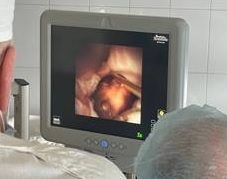

Ульяновские урологи начали применять новый метод при лечении мочекаменной болезни

В этом году врачи-урологи Ульяновского областного клинического центра специализированных видов медицинской помощи провели три успешные операции, применив новый метод, – интраренальную хирургию.

«На сегодняшний день ретроградная интраренальная хирургия является самым современным и эффективным методом хирургического лечения мочекаменной болезни, в том числе и в сложных случаях. Во время операции может использоваться как спинномозговая анестезия, так и общий наркоз. Главная задача – сохранить возможность управлять дыхательными процессами пациента и обеспечить при этом полное расслабление и отсутствие боли. Доступ к камню осуществляется через естественные мочевые пути: во время операции происходит минимальная травматизация мочевыделительных путей, что способствует скорейшему выздоровлению и максимально снижает риск послеоперационных осложнений», – рассказывает заведующий урологическим отделением УОКЦСВМП Александр Шмырин.

По словам специалистов, при интраренальной хирургической процедуре эндоскоп малого диаметра с лазером заводится в специальном кожухе, который защищает мочеточник и уретру, в мочевыделительные пути, чашечно-лоханочную систему почки после предварительного стентирования мочеточника.

«Безопасность процедуры, полное отсутствие кровопотери, минимальное воздействие на мочеточник и мягкие ткани благодаря применению гибкого инструмента, повторяющего все анатомические изгибы мочеточника при доведении его до почки, сочетаются с высокой эффективностью операции: режим лазерного дробления разрушает камни на мельчайшие частицы», - отмечают в пресс-службе министерства здравоохранения Ульяновской области.

Фото: минздрав